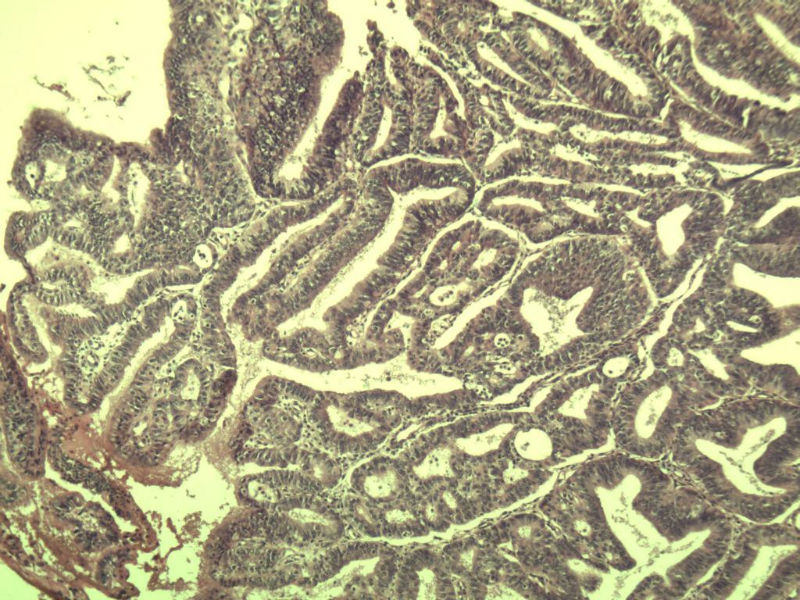

女 32岁 不规则阴道流血 一年  请各位老师看看 谢谢了

遵义医学院附属医院会诊结果    "复杂性增生伴非典型性 "

补充一下病史 病人10个月前因月经不规则行诊刮 诊断非典型性增生  上了曼月乐避孕环(好像是缓慢释放孕激素的那种),         都用激素治疗大半年了 还是这个样子 我还是觉得是癌  只有追踪一下以后病人的情况吧

高分化子宫内膜样癌

非典型复杂性子宫内膜增生,应了解雌孕激素情况。

子宫内膜复杂性非典型性增生,局灶区间质肉芽样(图5)及蜕膜样变,不够癌,建议临床查激素水平并追踪。

从照片看,没看到浸润的地方,我考虑是子宫内膜重度不典型增生。